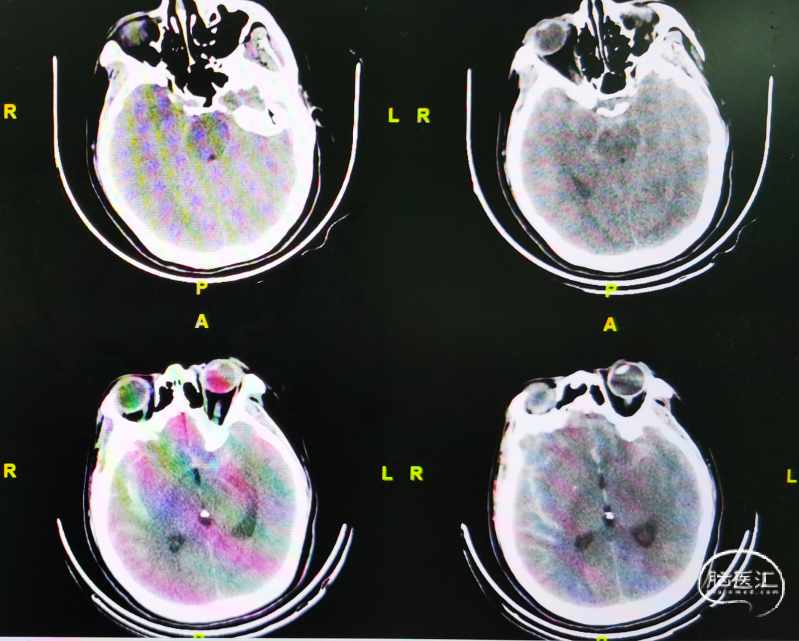

术前CT、CTA检查:

CT:蛛网膜下腔出血